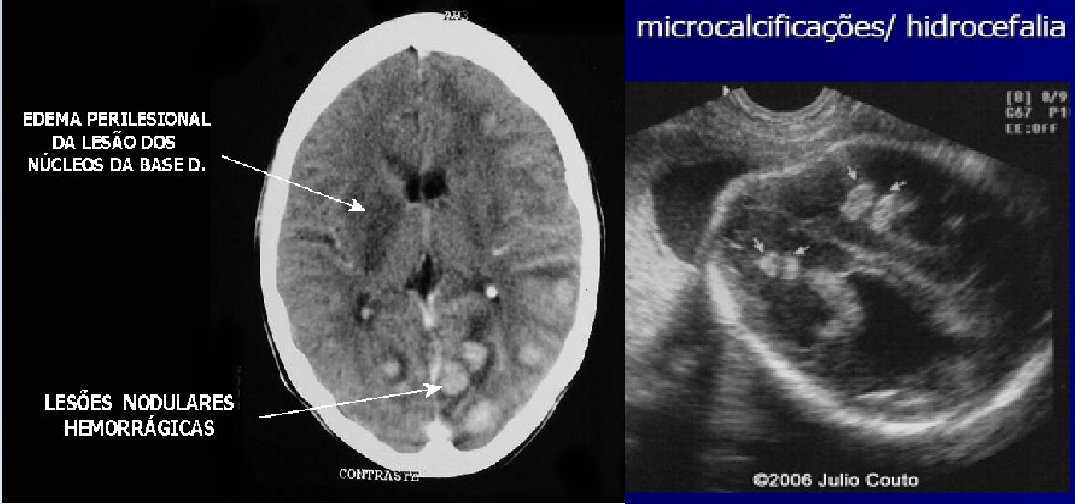

Lesões periventriculares

• Calcificações periventriculares (na toxoplasmose é intraparenquimatosa)

Lesões intraparenquimatosas

• Alterações no USG incluem: focos hiperecogênicos, hidrocefalia, rest, cresc, hepatoespenomegalia, ascite, calcificações intra hepáticas, hidropsia fetal